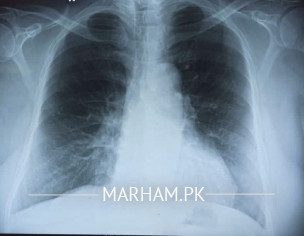

Patient developed symptoms 10 days ago with sore throat, a little fever on and off. Also having productive cough. COVID PCR was done 3 days ago with positive result. Oxygen saturation remains around 96-97. Attaching some xray and other tests requested. Please advise if any other action needed. current prescription attached. Previously before COVID test, he had been prescribed with Deltacort which is being continued by doctor till its full tenure